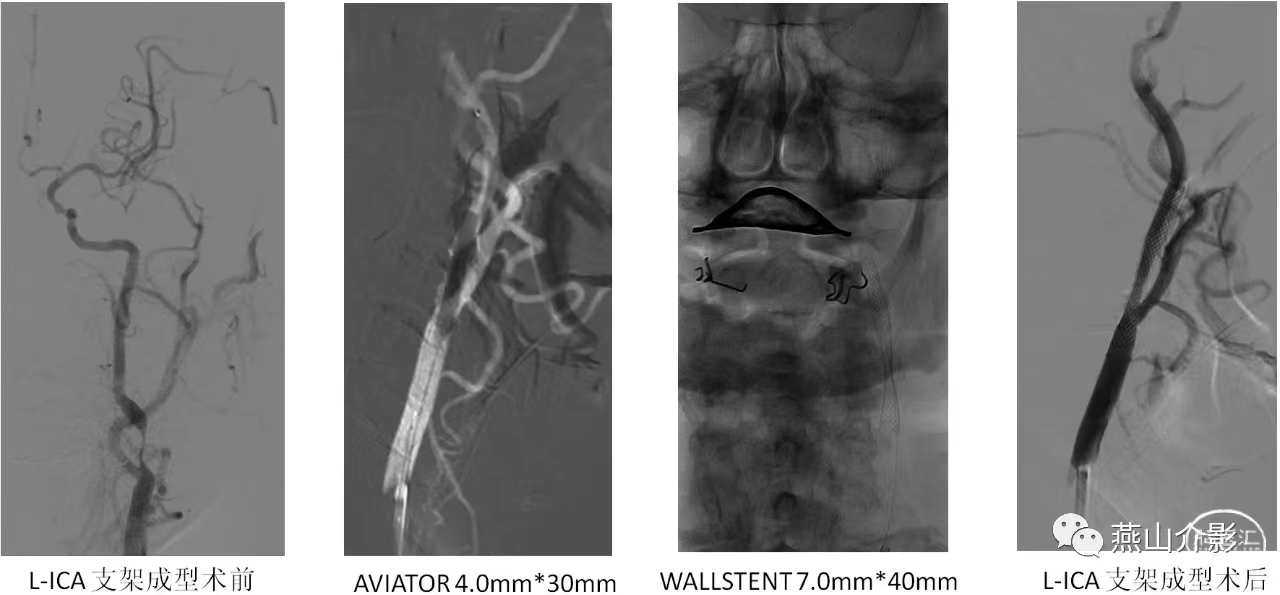

2019-11-05行L-ICA起始段狭窄支架成形术,支架植入前造影L-ICA起始段狭窄较球扩后加重。Spider5.0mm保护伞置于L-ICA C1段远端,Aviator 4.0mm×30mm球囊扩张狭窄段,而后置入WALLSTENT 7.0mm×40mm支架,术后即刻造影支架在位通畅,支架贴壁良好,残余狭窄。